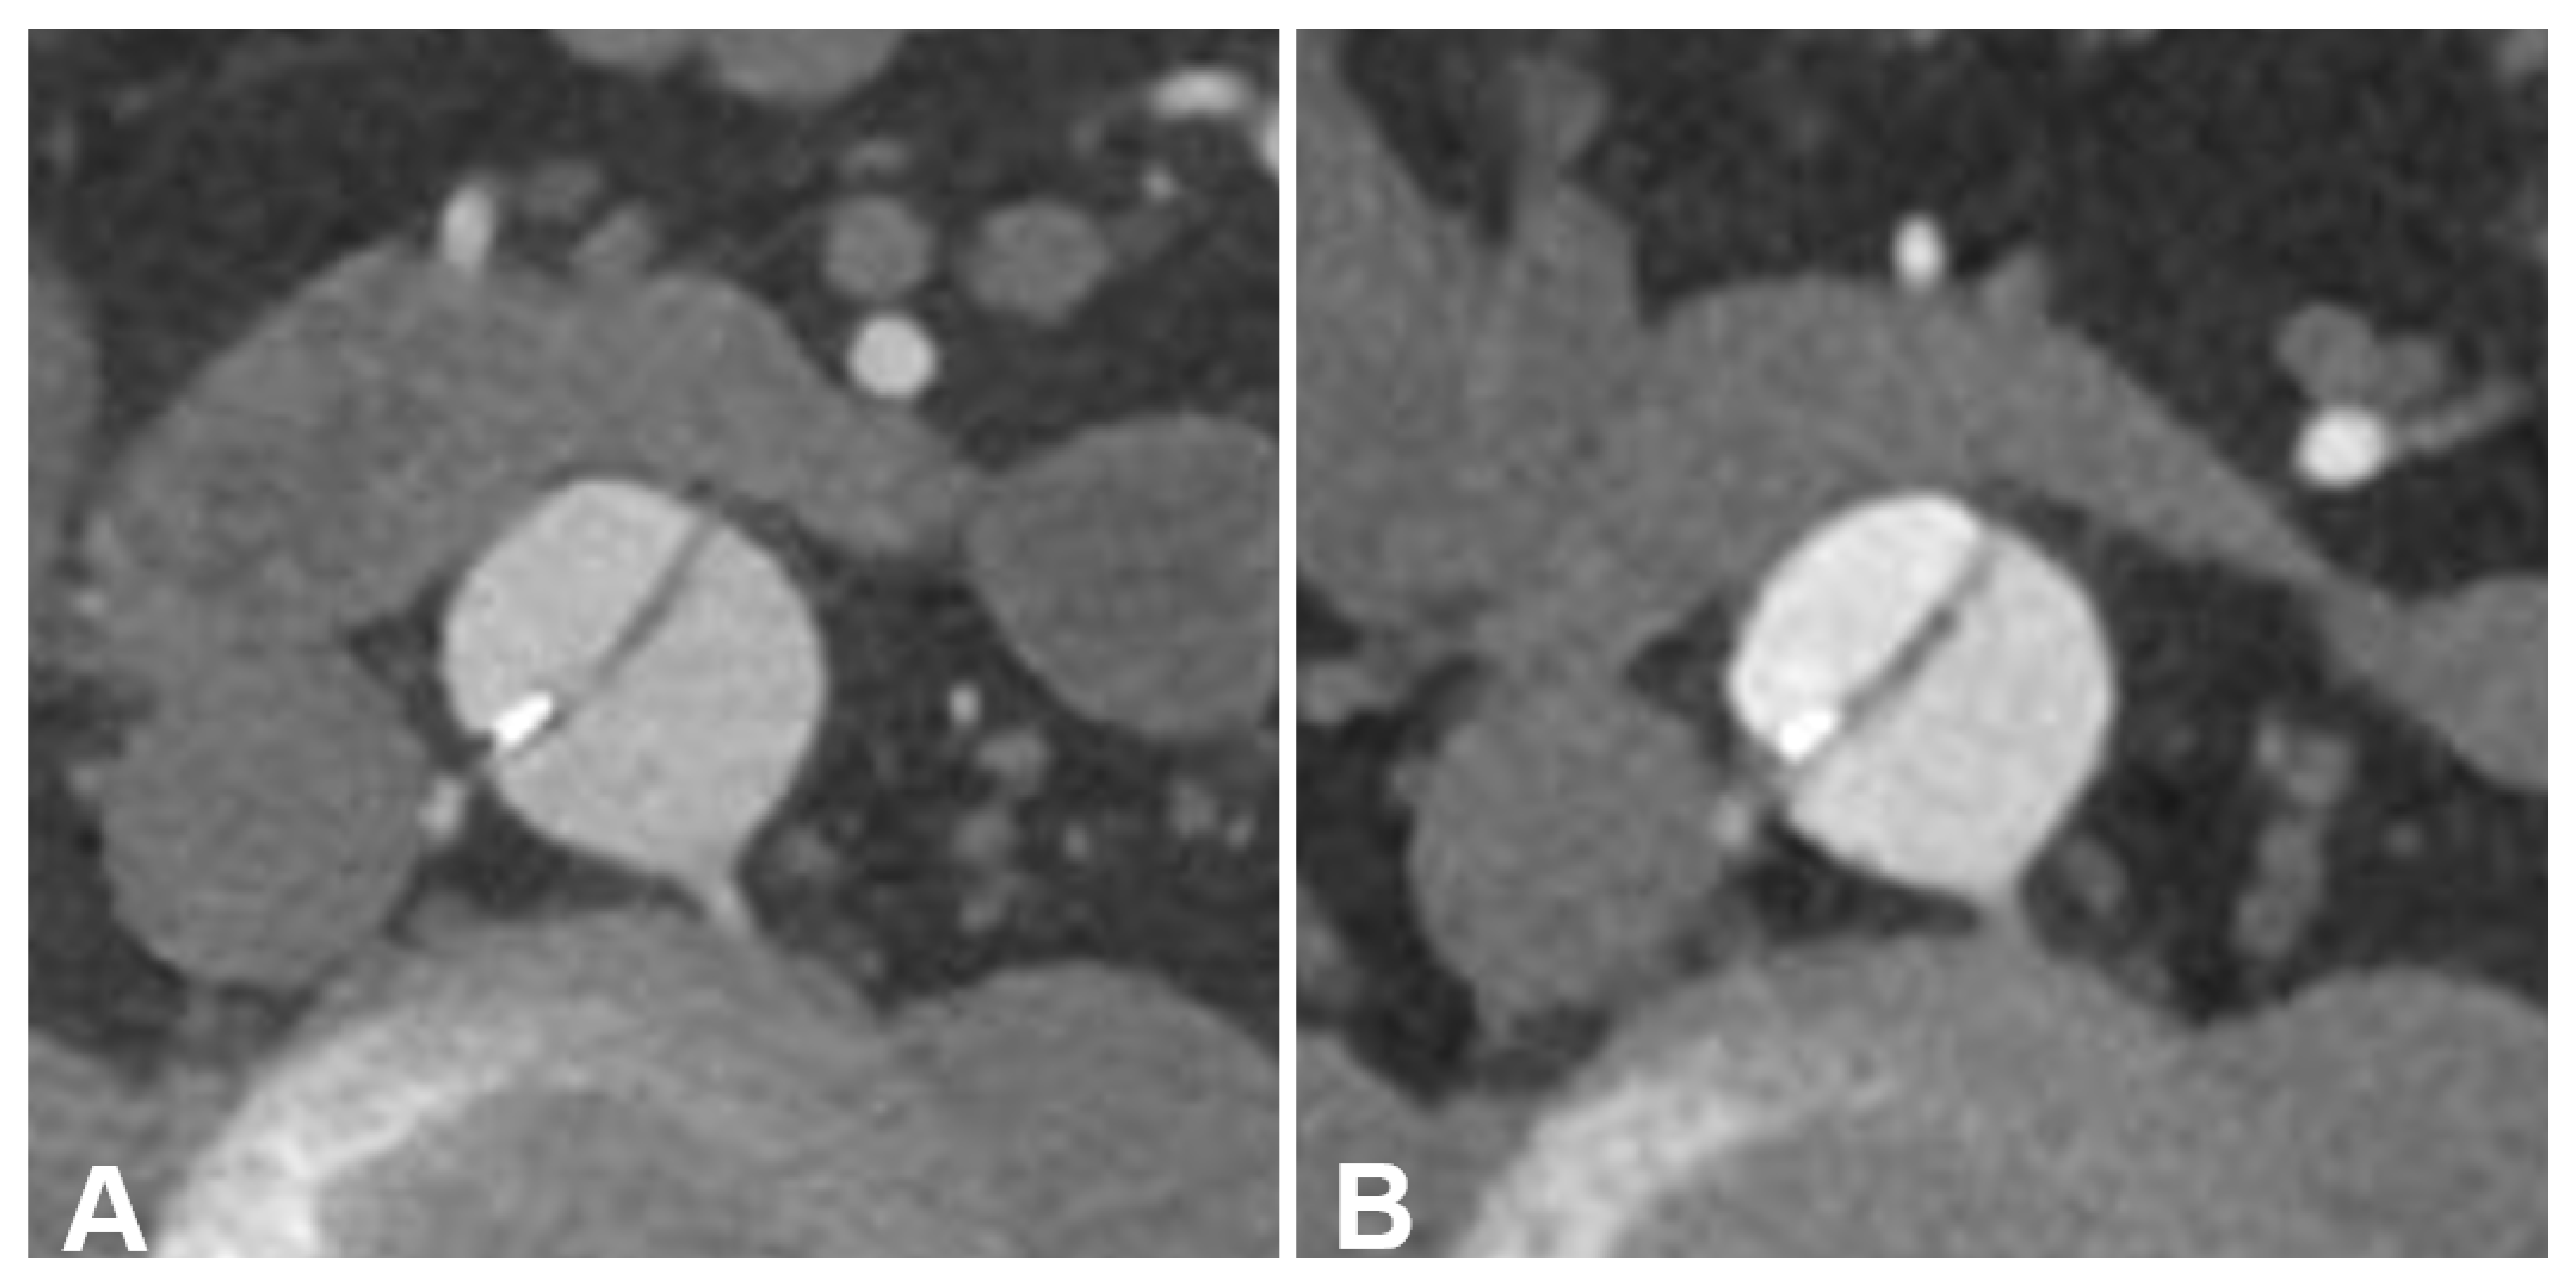

An Intra-Individual Comparison of Low-keV Photon-Counting CT versus Energy-Integrating-Detector CT Angiography of the Aorta

- Higashigaito, K.; Mergen, V.; Eberhard, M.; Jungblut, L.; Hebeisen, M.; Rätzer, S.; Zanini, B.; Kobe, A.; Martini, K.; Euler, A.; et al. CT Angiography of the Aorta Using Photon-counting Detector CT with Reduced Contrast Media Volume. Radiol. Cardiothorac. Imaging 2023, 5, e220140. [Google Scholar] [CrossRef] [PubMed]

- Euler, A.; Higashigaito, K.; Mergen, V.; Sartoretti, T.; Zanini, B.; Schmidt, B.; Flohr, T.G.; Ulzheimer, S.; Eberhard, M.; Alkadhi, H. High-Pitch Photon-Counting Detector Computed Tomography Angiography of the Aorta: Intraindividual Comparison to Energy-Integrating Detector Computed Tomography at Equal Radiation Dose. Investig. Radiol. 2022, 57, 115–121. [Google Scholar] [CrossRef]

- Dunning, C.A.S.; Rajendran, K.; Inoue, A.; Rajiah, P.; Weber, N.; Fletcher, J.G.; McCollough, C.H.; Leng, S. Optimal Virtual Monoenergetic Photon Energy (keV) for Photon-Counting-Detector Computed Tomography Angiography. J. Comput. Assist. Tomogr 2023, 47, 569–575. [Google Scholar] [CrossRef]

- Dillinger, D.; Overhoff, D.; Booz, C.; Kaatsch, H.L.; Piechotka, J.; Hagen, A.; Froelich, M.F.; Vogl, T.J.; Waldeck, S. Impact of CT Photon-Counting Virtual Monoenergetic Imaging on Visualization of Abdominal Arterial Vessels. Diagnostics 2023, 13, 938. [Google Scholar] [CrossRef] [PubMed]